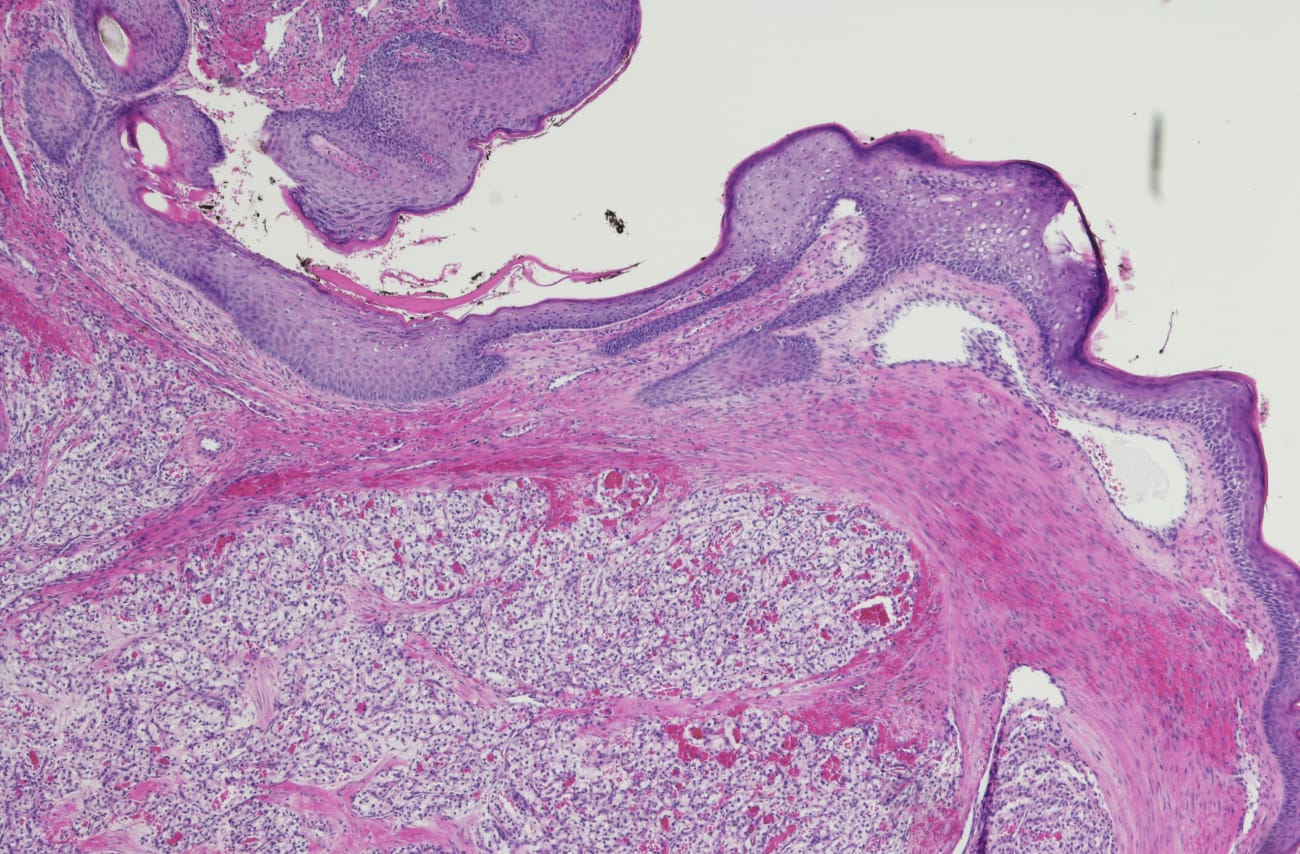

The most prominent form of kidney cancer is clear cell renal cell carcinoma (ccRCC), and Hopkins investigators are part of a team that has delineated the molecular profiles of ccRCC. The work, done as part of the National Cancer Institute’s Clinical Proteomic Tumor Analysis Consortium initiative, was published in Cell. The paper’s first author was David Clark, Ph.D., a postdoctoral fellow in the lab of Hui Zhang, M.S., Ph.D., Director of the Mass Spectrometry Core Facility in the Center for Biomarker Discovery and Translation.

Not only did the team identify several novel aspects of ccRCC biology, but “this represents the first major, large-scale proteogenomic characterization of ccRCC,” explains urologist and clinical collaborator Phillip Pierorazio, M.D. “Many of the genetic alterations of kidney cancer are known, but this research demonstrates how those genetic alterations trickle down to proteins and active functions of the cells that define a kidney cancer.” The implications of this research are exciting, he adds: “It tells us much more about potential targets for diagnosis and therapy than we previously knew.”